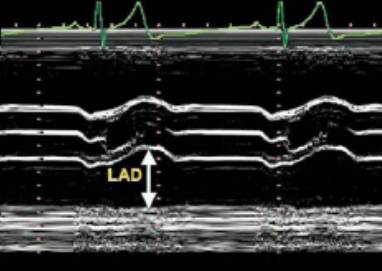

11、左心房的径线测量

测量位置:胸骨旁长轴切面。

测量时相:收缩末期左房最大时。

正常值:LA(左房)小于等于34mm。

LA前后位径线的增大可被胸骨和脊柱间的胸腔所限制,使得前后位径线可能无法代表LA大小,应与容量测定结合使用。